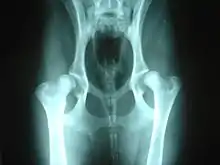

Dysplastic hip anatomy

The hip could have major contractions from dysplasias. The caput is not deeply and tightly held by the acetabulum. Instead of being a snug fit, it is a loose fit, or a partial fit. Secondly, the caput or acetabulum are not smooth and round, but are misshapen, causing abnormal wear and tear or friction within the joint as it moves.[2] The body reacts to this in several ways. First, the joint is continually repairing itself and laying down new cartilage. However, cartilage repair is a relatively slow process, the tissue being avascular, so the joint may suffer degradation due to the abnormal wear and tear, or may not support the body weight as intended. The joint becomes inflamed and a cycle of cartilage damage, inflammation and pain commences. This is a self-fueling process, in that the more the joint becomes damaged, the more damage it will cause to the surrounding tissues and bones. The inflammation also causes further damage. The bones of the joint may also develop osteoarthritis, visible on a radiograph as small outcrops of bone, which further degrade the joint.[3] Osteoarthritis is a degenerative disease marked by the breakdown of cartilage between joints resulting in painful bone-to-bone contact.[4]